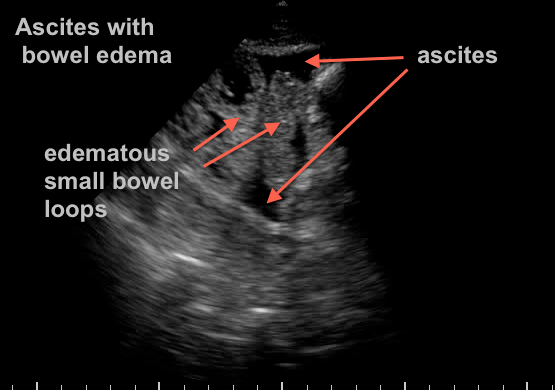

73 yr old woman recovering from septic shock with abdominal distension and difficulty tolerating enteral feeds…

what do you see?

Extensive third spacing from resuscitation has resulted in bowel edema and ascites.  Another “benign” effect of massive crystalloid use… A bedside 22g US guided tap confirms benign transudate.